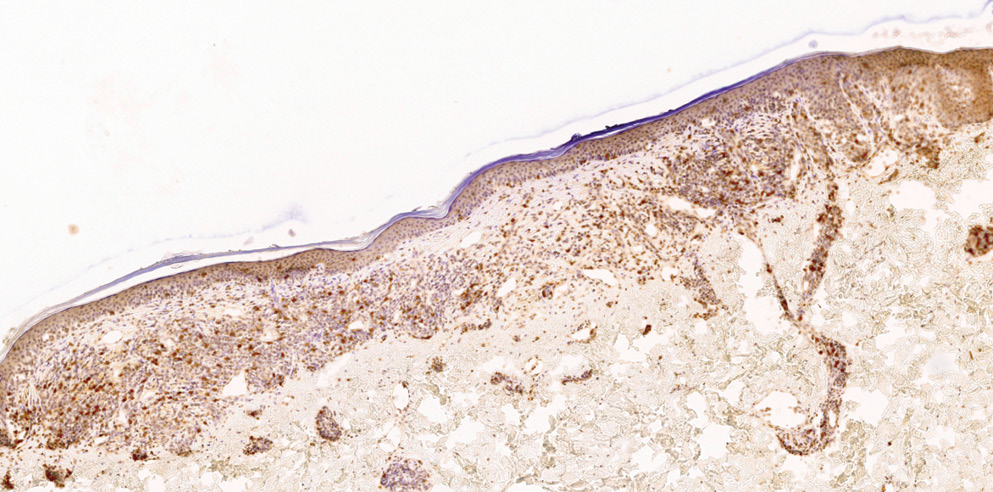

Выполнено иммуногистохимическое исследование. По результатам ИГХ-исследования от 23.12.2022: иммунофенотип клеток инфильтрата соответствует грибовидному микозу (подавляющее большинство клеток инфильтрата имеют фенотип CD5+CD4+CD8–CD30–) (рис. 7, 8). Индекс пролиферативной активности клеток инфильтрата (по Ki67) — около 5%.

Рис. 7. Иммуногистохимическое исследование CD4

Fig. 7. CD4 immunohistochemistry

Рис. 8. Иммуногистохимическое исследование CD8

Fig. 8. CD8 immunohistochemistry